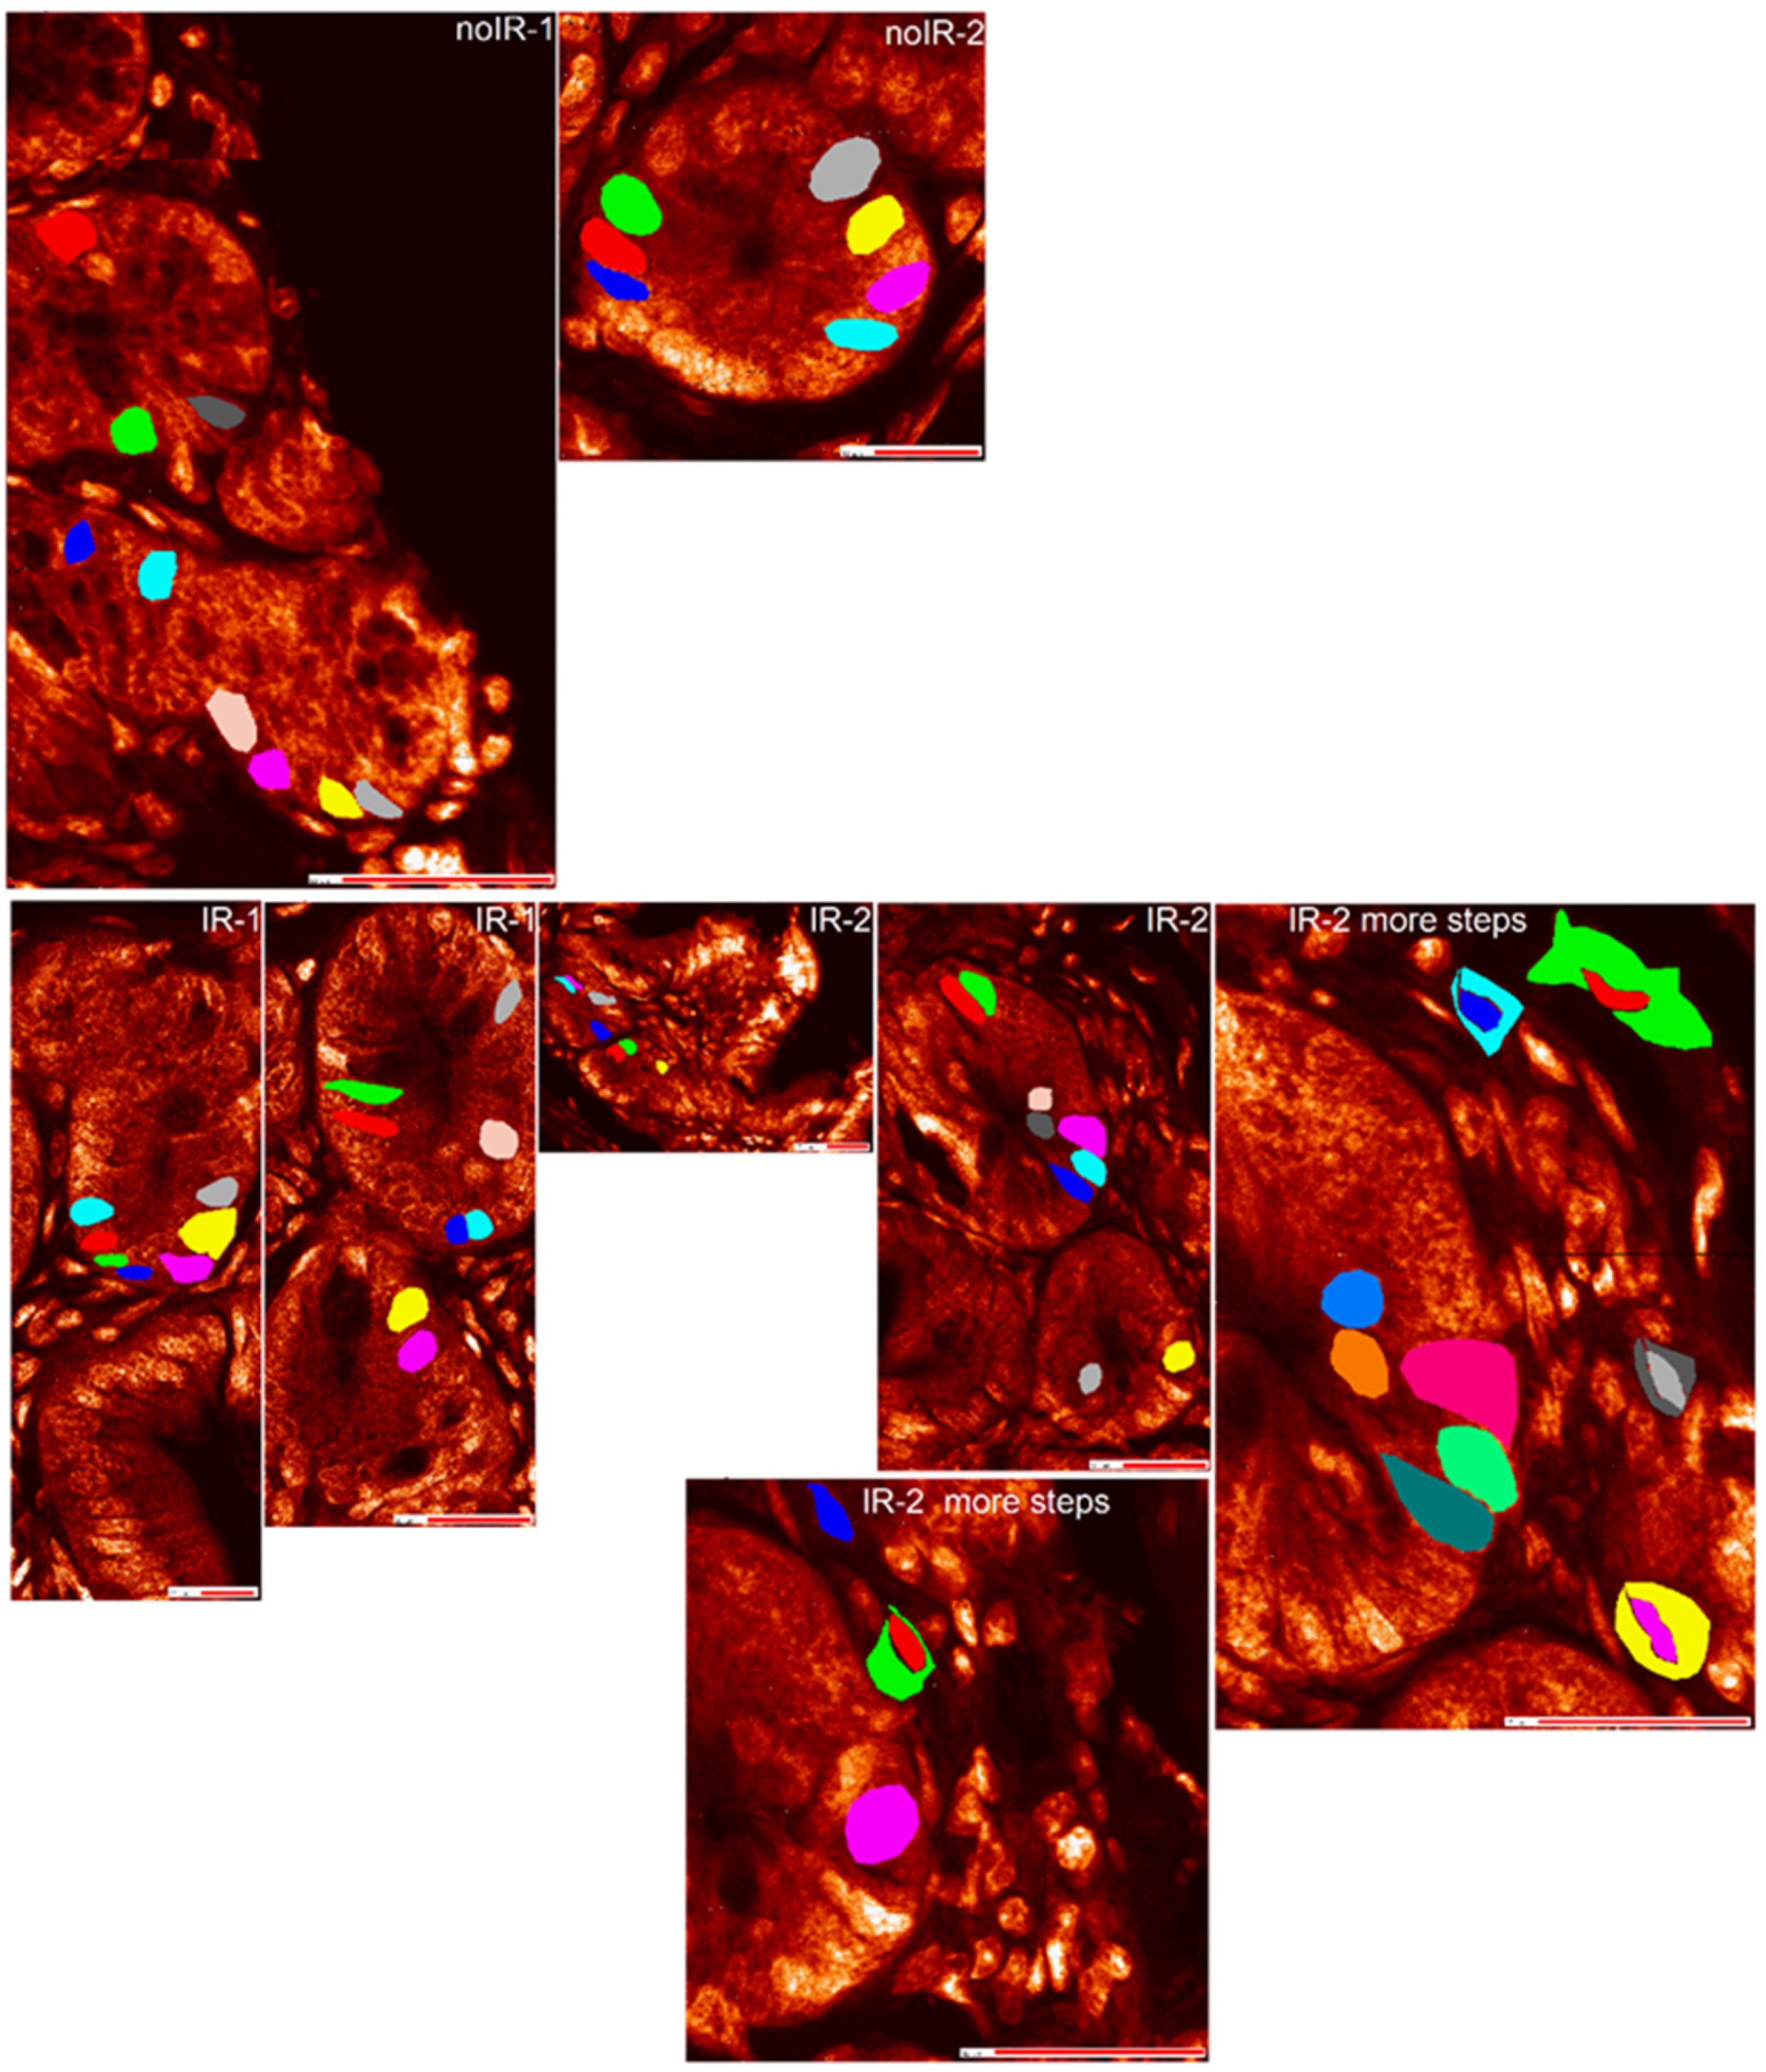

2.2.1. Mean Pixel Concentration Analysis—Cell Type Analyses

2.2.2. Mean Pixel Concentration Analysis—Individual Cell Analyses

2.2.3. ANOVA Evaluation of Cell-to-Cell Elemental Differences